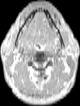

Visible Human male: Sectio transversalis 1202

CT

NMR

Pd T1 T2